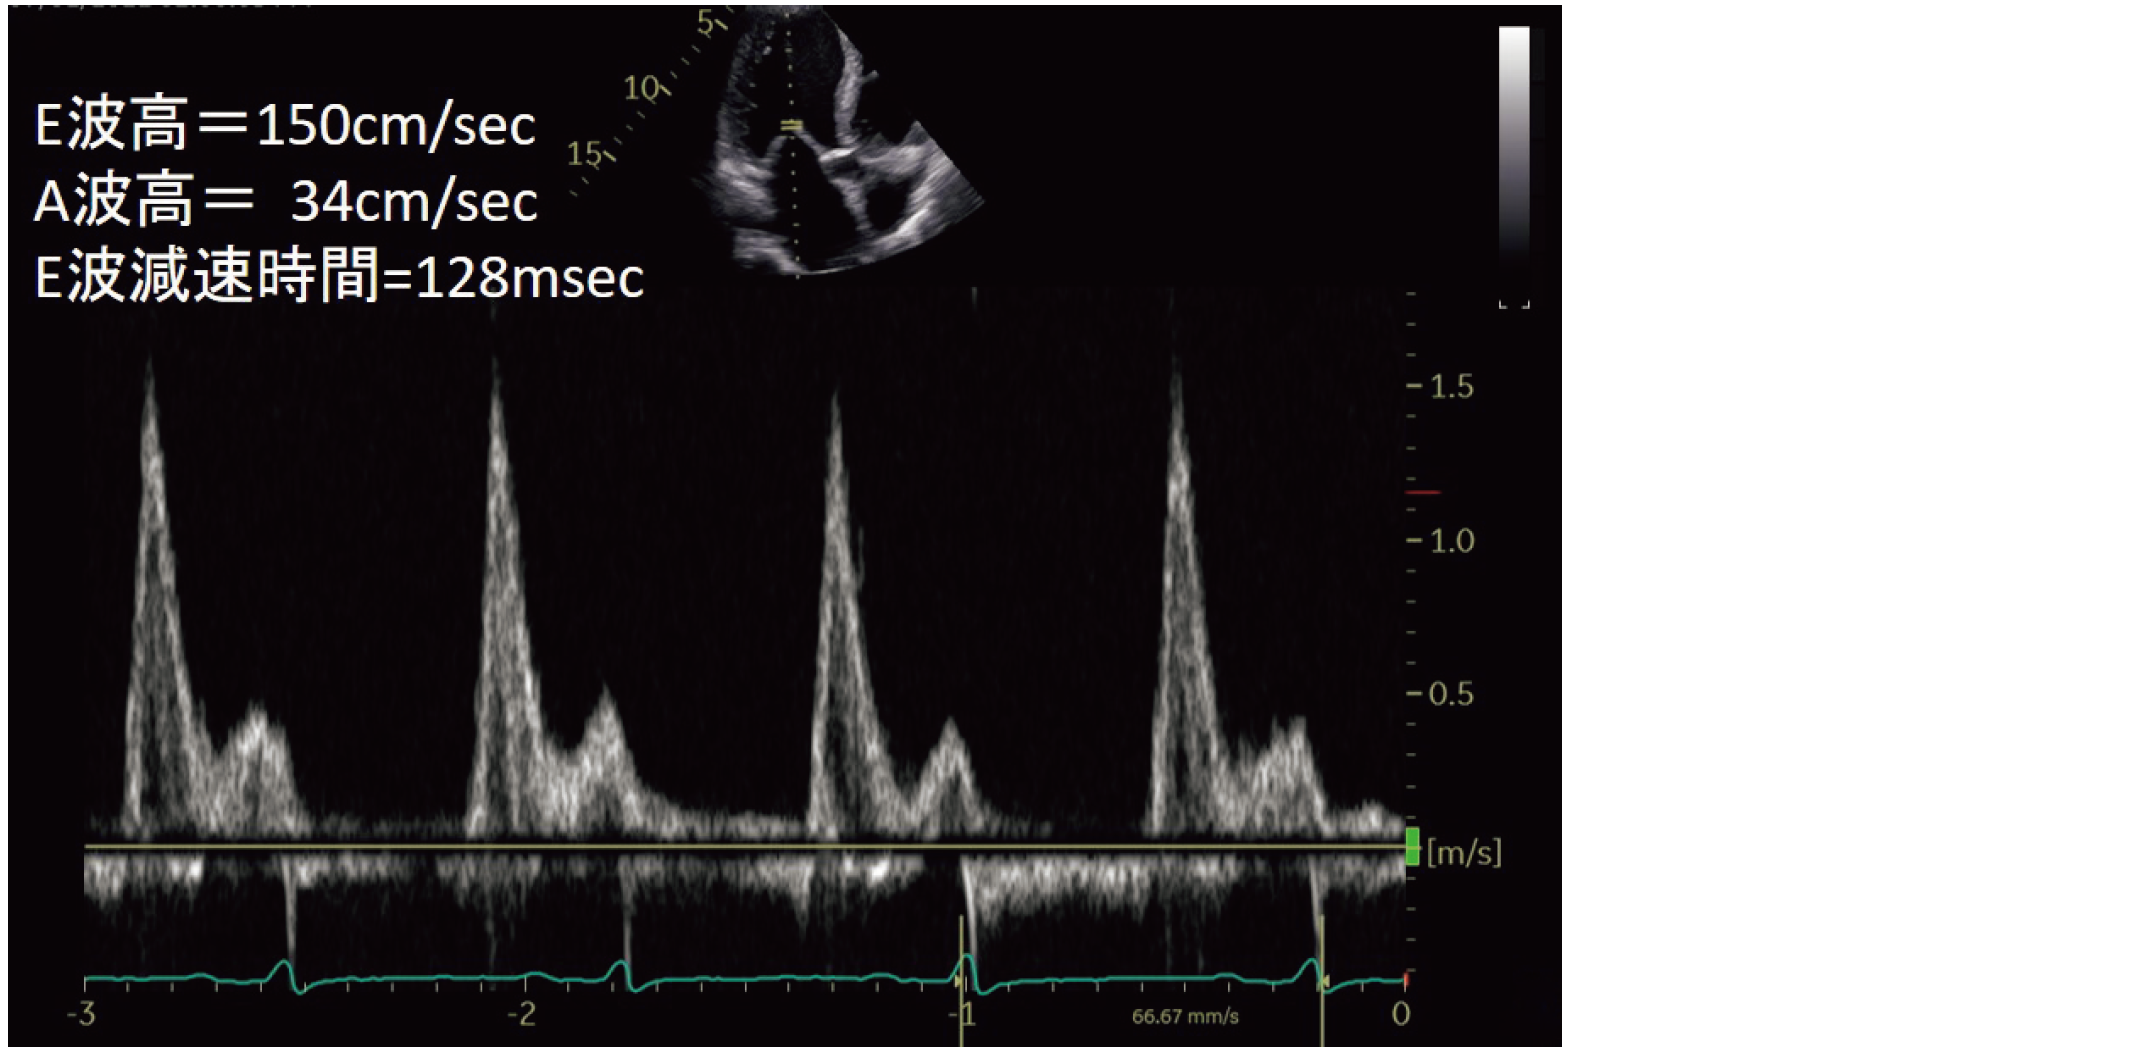

78歳の男性。心不全患者の左室流入血流速波形と計測値を示す(ID 2023024,ID 2023025共通)。

この波形の記録に用いたのはどれか。